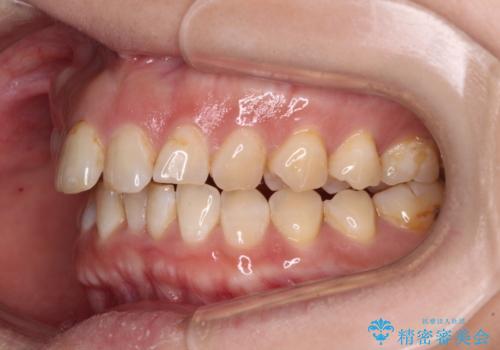

- 飛び出た上の前歯を気にして来院された患者様です。

奥歯の咬み合わせは、上顎歯列が理想的な一よりも数mm前方にある状態でした。

なるべく早めに治療を終えたいとのことで、補助装置を用いて上顎臼歯を後方に移動させ、同時にワイヤー装置にて整えることとしました。

舌の突出癖が原因で上下の歯に大きなスペースが生じていたため、舌のトレーニングをしっかり行っていただくことで、上顎歯列をスムーズに移動させることができました。